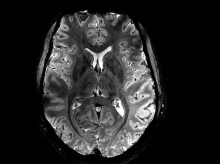

Ongekend scherp beeld van de hersenen uit een Franse MRI-scanner 18 mei 2024 - 08:07Bron NRC | Zó gedetailleerd zag de wereld de hersenen nooit eerder op een MRI-scan.